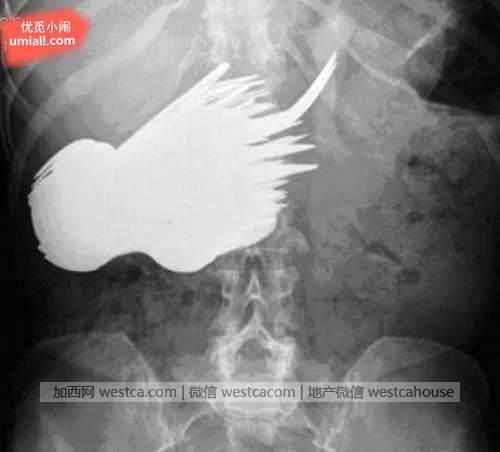

1. 这个女性的胃里有78支刀叉…

晚餐吃太快了?